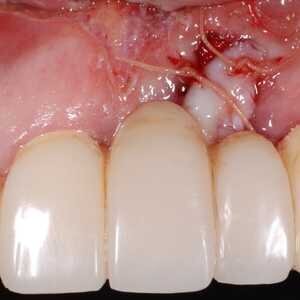

Dans cet article, nous présentons un cas clinique qui montre comment une mauvaise mise en place d'un implant peut rendre impossible la réhabilitation prothétique, ce qui nécessite une nouvelle planification chirurgicale et de réhabilitation pour obtenir l'esthétique souhaitée. Le patient se présente à notre observation avec une réhabilitation prothétique incongrue, avec bride en résine, support dentaire et implantaire, avec la présence d'un implant en position 2.1 vestibulaire et avec l'émergence dans le fornix, dans la mucosa alvéolaire. L'évaluation de la tomodensitométrie montre la position incorrecte de l'implant et la perte constante dans le sens transversal de la structure osseuse (Figs. 1, 2). Par conséquent, le plan de traitement suivant a été choisi : retrait de l'implant et préparation prothétique de l'élément 2.3, fabrication d'un premier support dentaire temporaire pour guider la cicatrisation des tissus (Figs. 3-7). Après 4 mois, une greffe d'épithélium conjonctif libre est réalisée avec ablation du palais pour compenser l'espace transversal des tissus mous, puis le provisoire est remodelé afin de faciliter la cicatrisation des tissus (Figures 8-11). Après 9 mois de maturation des tissus, la finalisation prothétique fixe avec support dentaire est réalisée (Figs. 12-14).